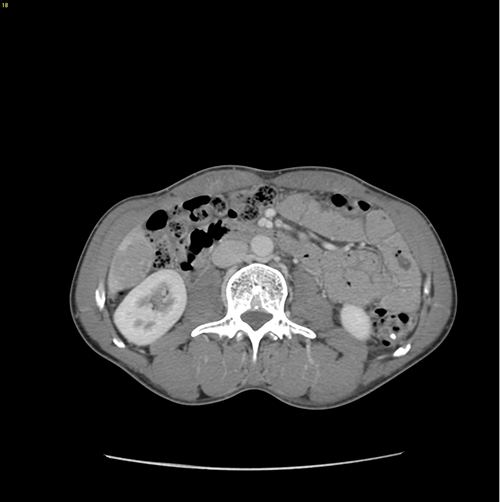

S6肝癌--腹腔镜S6部分切除